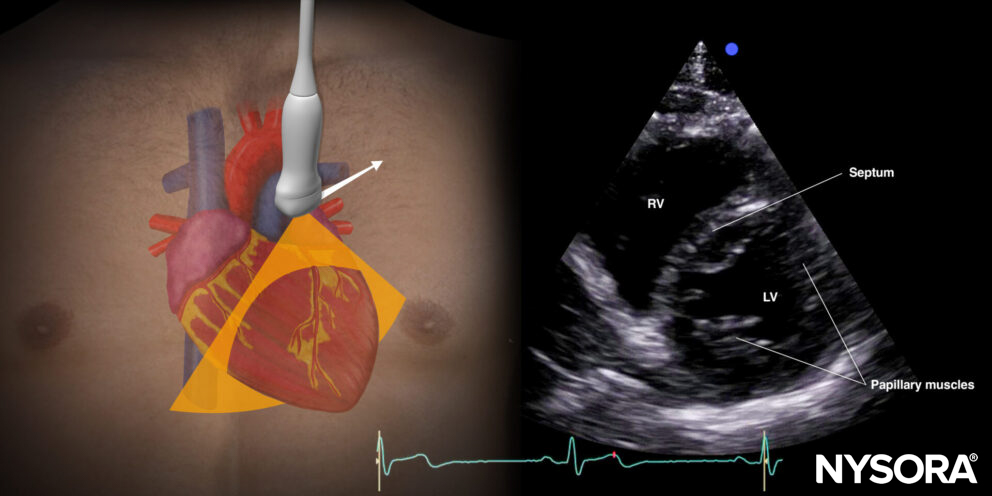

Parasternal short-axis view (PSAX): mitral and aortic valves

Transducer position and sonoanatomy of the parasternal short-axis view.